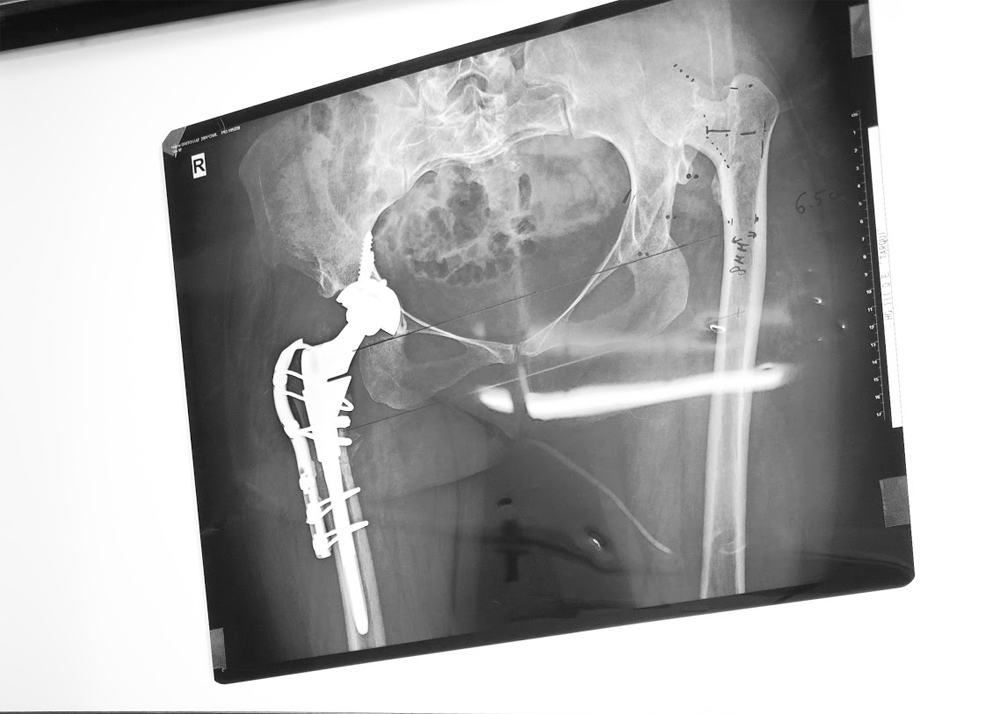

Four surgeries were performed today however, for efficiencies one of today’s cases was swapped into tomorrow’s schedule, and one of Sunday’s patients slotted into today. Fortunate that the patient booked for Sunday was in the hospital for further assessment – B. L. received her shortening osteotomy surgery one day early.